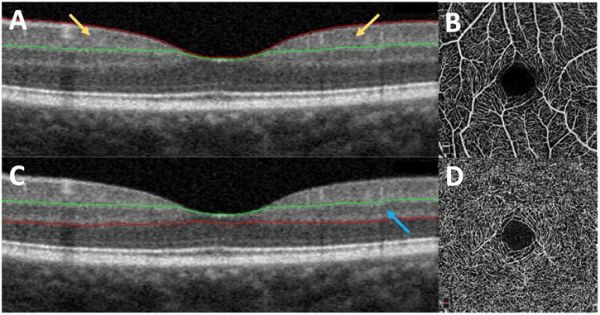

Spectral Domain and Enhanced Depth Imaging Optical Coherence Tomography

Signs of DMI may be apparent in the retinal microstructure when viewed through SD-OCT. Fawzi et al. looked at DMI as a cause of photoreceptor compromise and outer retinal changes.[57] They identified the area of ischemia seen through FA, OCTA, and adaptive optics scanning laser ophthalmoscopy (AOSLO), then mapped the corresponding area viewed through SDOCT. In areas of non-perfusion, there was an associated disruption of the external limiting membrane, IS/OS junction, along with thinning of the inner retina, photoreceptors, and ONL.[57][58][59] See Figure 8 for an illustrative example. In contrast, a study by Dmuchowska et al. showed that SDOCT measurements of thickness and structure could not predict the FAZ size and outline, with the detection of DMI still reliant on FA or OCTA.[60]